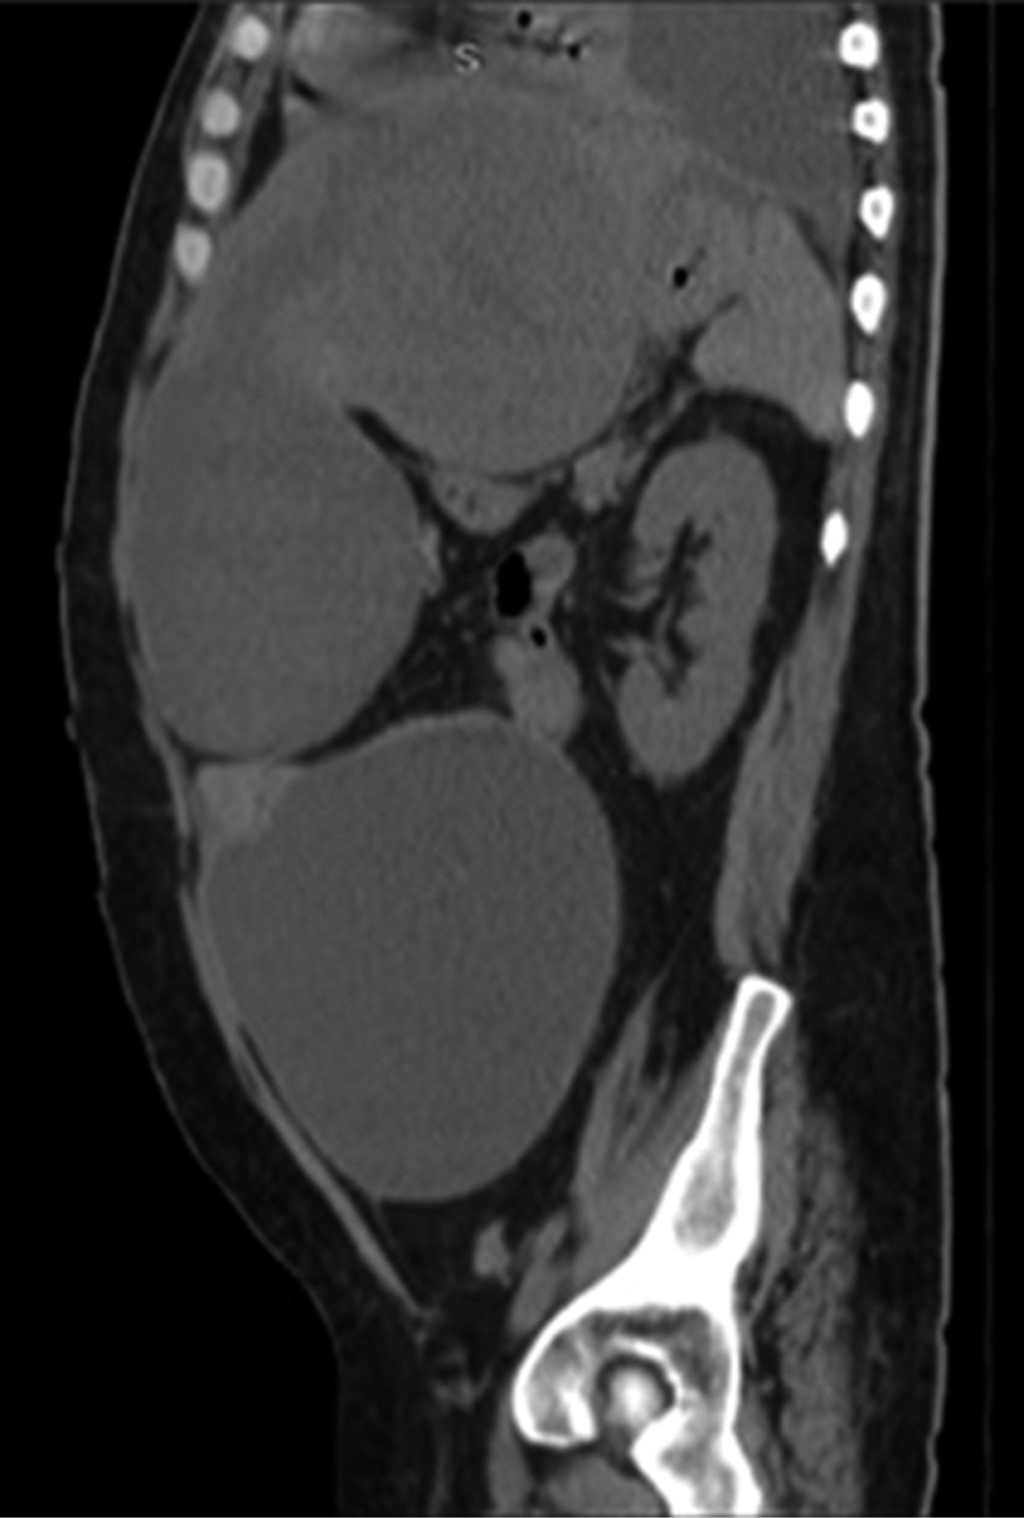

An anteroposterior (AP) chest X-ray was performed, in which a left pleural effusion covering more than 50% was visualized. A computed tomography scan showed a significant amount of fluid in the left pleural space that conditioned a passive atelectasis of the lower lobe (Figure 1); the liver was found with heterogeneous density with an increase of the left hepatic lobe secondary to the presence of a heterogeneous hypodense lesion with lobulated borders, showing peripheral reinforcement and some internal septa covering segments II, III, IVa, and IVb measuring approximately 20 × 14.5 × 12.5 cm (Figure 2), conditioning posterior displacement and compression of the stomach and pancreas and caudal displacement of the intestinal loops (Figures 3 and 4). In the lower pole of the right hepatic lobe adjacent to segment IV, a homogeneous cystic lesion with peripheral enhancement was identified after intravenous contrast administration, measuring 25 × 27 × 13 cm in its major axes. A Foley tube and nasogastric tube were placed as initial management draining a liquid of gastric characteristics (30 ml). A central catheter was placed and verified by radiography. Imaging studies were requested. Fasting was ordered and fluid therapy, antibiotic therapy with ceftriaxone and metronidazole, pain management, glycemic control, and gastric protection were started. When visualizing the image of the left pleural effusion, it was decided to perform a thoracentesis, obtaining a thick exudate with a chocolate appearance. When the tomography was available, urgent surgical treatment was performed.

Figure 4